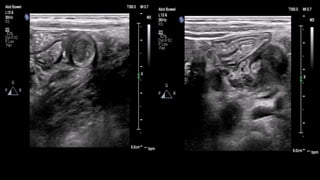

This document discusses the evaluation of right lower abdominal pain and lists appendicitis as a key cause. It notes that other potential causes include hemorrhagic cysts, heterotrophic pregnancy, salpingitis with pyosalpinx, funiculitis, and torsion of an undescended testis. The document was presented by Dr. A.S.M. Sufian of Cumilla Medical College Hospital and thanks the audience for their patience and listening.